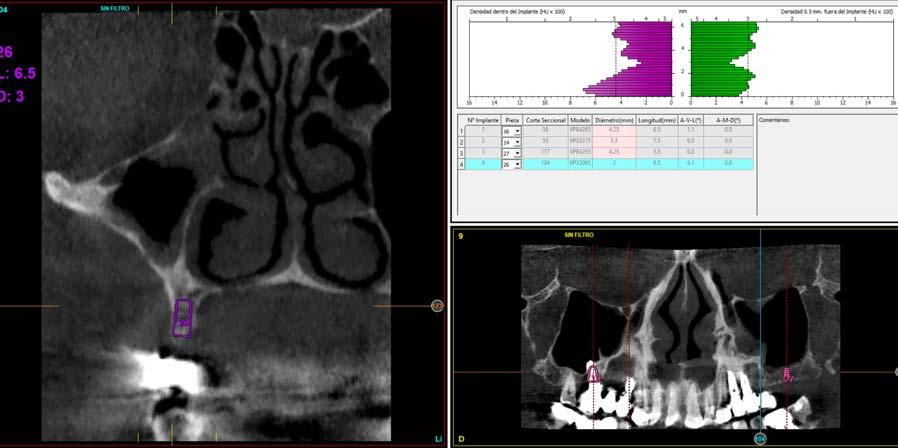

Issuu converts static files into: digital portfolios, online yearbooks, online catalogs, digital photo albums and more. Sign up and create your flipbook.